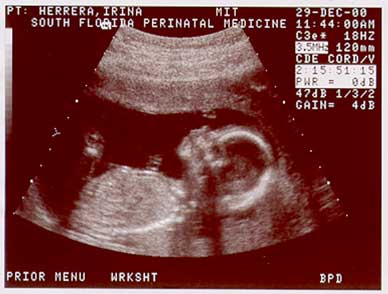

These images show the baby at 17wks. (Dec. 29, 2000) |

Image sequence 2 of 3 |